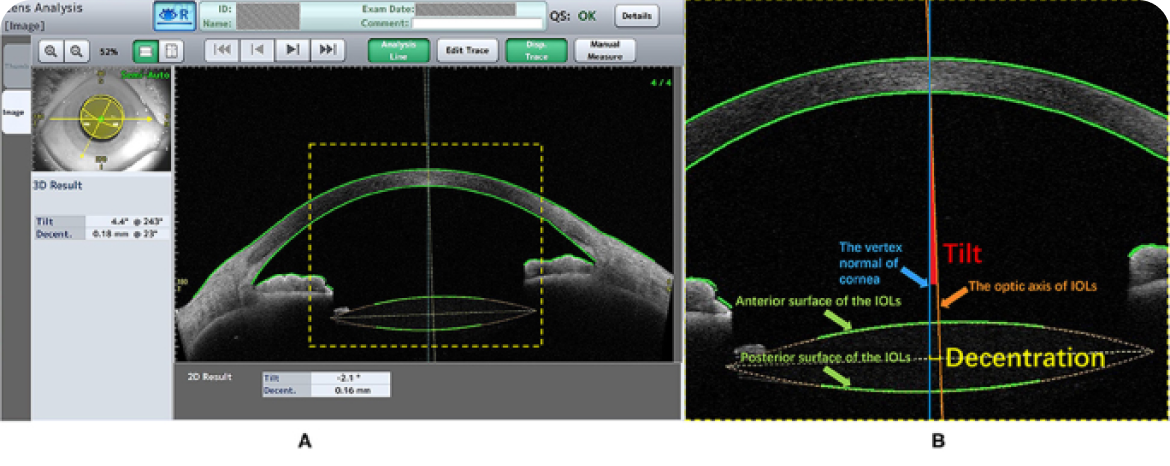

수술 후 안내렌즈(IOL)의 중심잡기와 기울임(Decenteration & Tilt)을

닥터 ICL 안과의 고해상도 CT “CASIA2”로 평가하는 모습

고기능 인공수정체(근시,원시,난시,노안 동시 교정, 3중초점, 4중 초점, 연속초점 IOL등) 는 안구 내 중심잡기와 기울어짐에 따라

같은 도수라도 시력의 질이 많이 차이가 날 수 있기 때문에 위 그림과 같은 측정이 꼭 필요합니다.